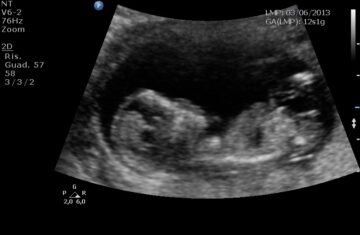

Oggi, 3 anni dopo, assieme alla mia compagna sono riuscita davvero a dare alla luce quella piccola anima che tanto ho lottato per abbracciare… ed ogni momento di sconforto e smarrimento vissuto, ammetto di aver pensato più di una volta a queste sue parole.